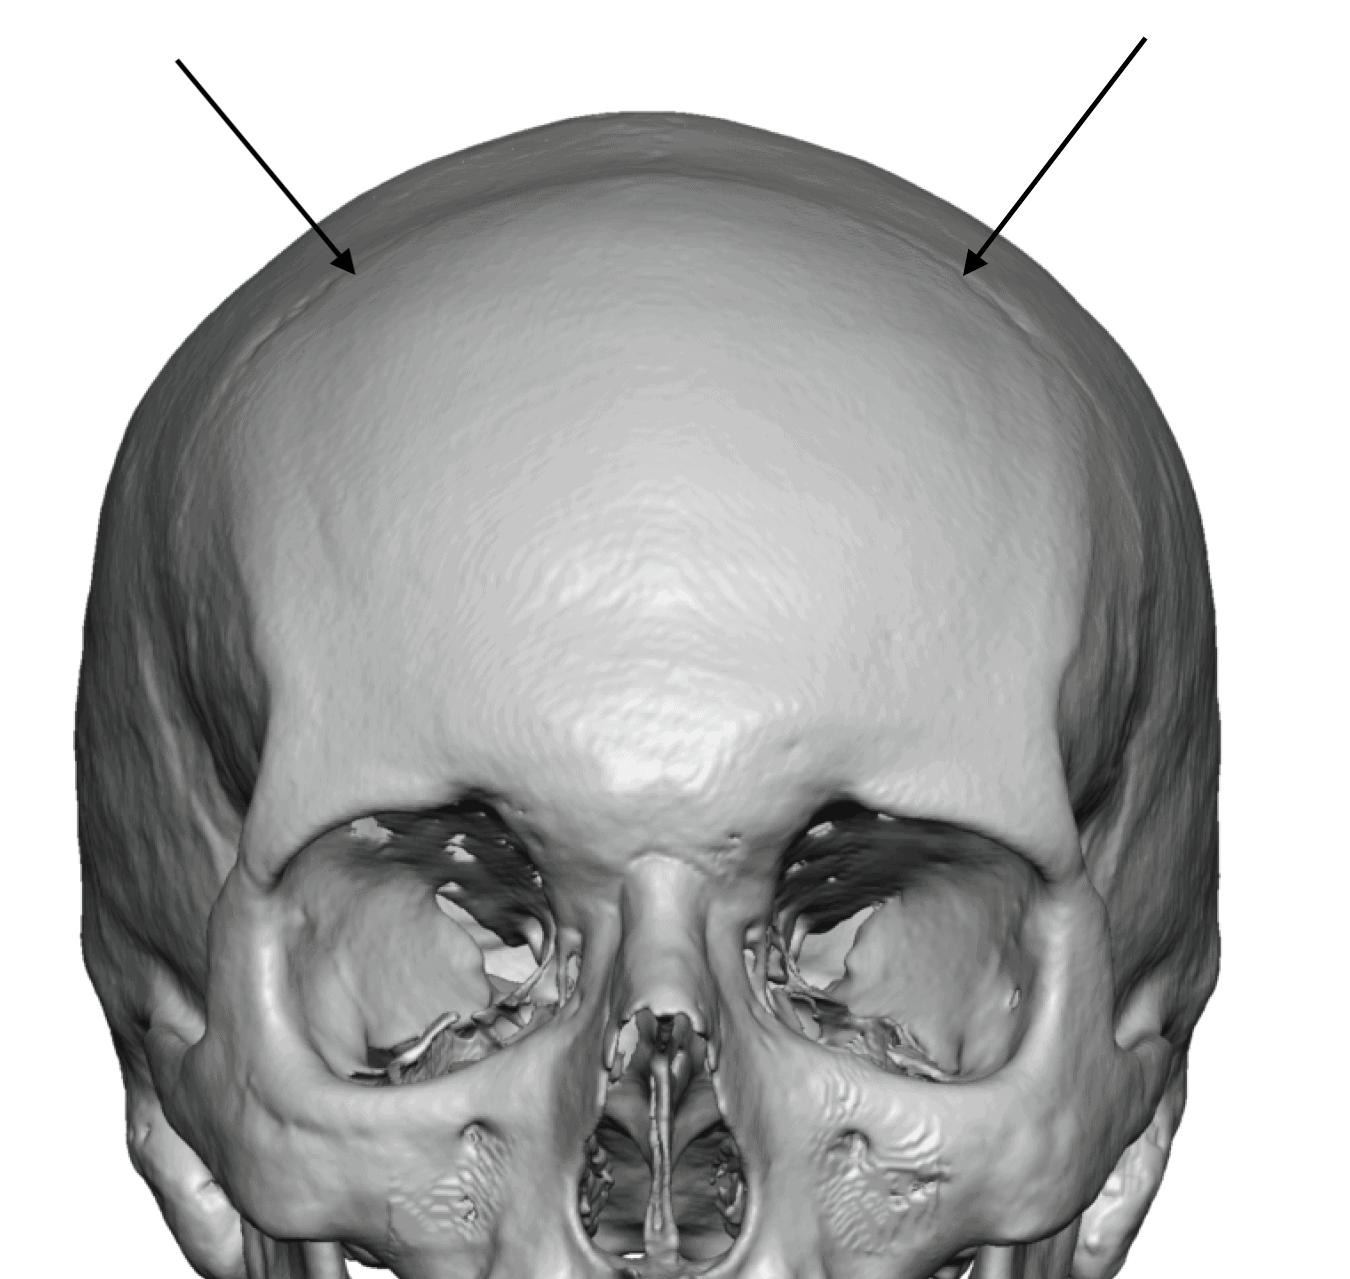

Patient 28

Desire for rounder shape to the top of the head from a congenital parasagittal deficiency skull shape.

Custom skull implant designed to fill in the parasagittal deficiencies.

Desire for rounder shape to the top of the head from a congenital parasagittal deficiency skull shape.

Custom skull implant designed to fill in the parasagittal deficiencies.